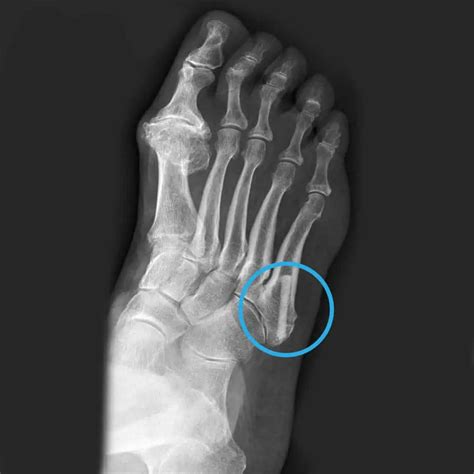

Experiencing a broken metatarsal bone can be an incredibly painful and disruptive event in your daily life. The metatarsals are the five long bones in the midfoot that connect your ankle area to your toes, acting as the foundation for your weight-bearing activities. When one of these bones fractures, the impact on your mobility is immediate. Whether the injury resulted from a sudden trauma, such as dropping a heavy object, or a repetitive stress injury common in athletes, understanding the nature of your break is the first step toward a successful recovery.

The metatarsals are categorized by their location, usually numbered one through five, starting from the big toe side. Because these bones are essential for balance and gait, a fracture in any of them can significantly alter how you walk. While some fractures are stable and heal with minimal intervention, others may be displaced, meaning the bone fragments have shifted out of their normal alignment, potentially requiring specialized care.